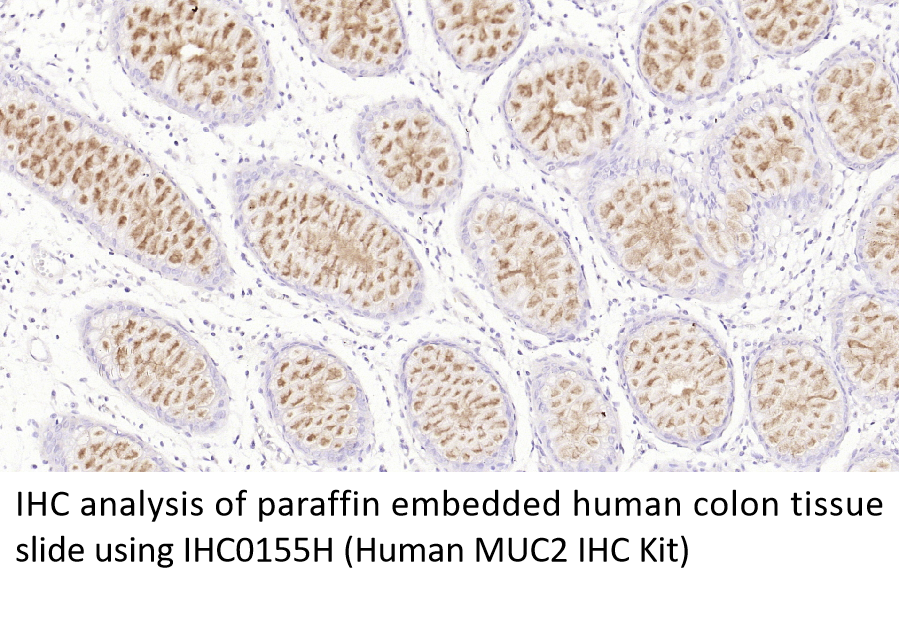

MUC2

结直肠癌(colorectal cancer, CRC):胃肠道中常见的恶性肿瘤,包括结肠癌和直肠癌。癌瘤大多数为腺癌,少数为鳞状上皮癌及粘液癌。结直肠癌的发病率从高到低依次为直肠、乙状结肠、盲肠、升结肠、降结肠以及横结肠,近年有向近端(右半结肠)发展的趋势。其发病与生活方式、遗传、大肠腺瘤等关系密切。发病年龄趋老年化,男女之比为1.65:1。 结直肠癌早期无症状,或症状不明显,仅感不适、消化不良、大便潜血等。随着癌肿发展,症状逐渐出现,结直肠癌因部位不同而表现出不同的临床症状及体征。肿瘤因转移、浸润可引起受累器官的改变。 结直肠癌的发生与高脂高蛋白低纤维素饮食、大肠慢性炎症、大肠腺瘤、遗传因素和其他因素如:血吸虫病、盆腔放射、环境因素(如土壤中缺钼)、吸烟、年龄因素、肥胖及化学物质等有关。02 结直肠癌常用肿瘤标志物

5.BETGE, Johannes, et al. MUC1, MUC2, MUC5AC, and MUC6 in colorectal cancer: expression profiles and clinical significance. Virchows Archiv, 2016, 469: 255-265.

6.MOEHLE, Christoph, et al. Aberrant intestinal expression and allelic variants of mucin genes associated with inflammatory bowel disease. Journal of molecular medicine, 2006, 84: 1055-1066.

7.VELCICH, Anna, et al. Colorectal cancer in mice genetically deficient in the mucin Muc2. Science, 2002, 295.5560: 1726-1729.